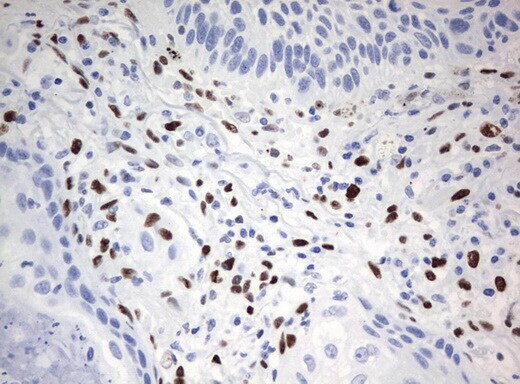

- Immunohistochemical staining of paraffin-embedded Carcinoma of Human lung tissue using anti-ZSCAN18mouse monoclonal antibody. (UM500081; heat-induced epitope retrieval by 10mM citric buffer, pH6.0, 120°C for 3min)